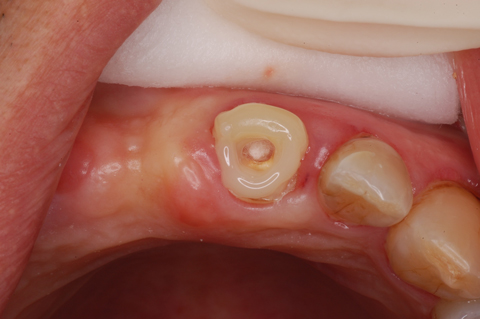

前歯のさし歯が取れたとか折れたとかだと、こんなになります。

根だけ残ってる状態です。

ですからこのように隔壁尚かつ支台のようなビルドアップをして仮歯を入れなくてはなりません。

この後穴を塞いで周りを形成して仮歯を入れます。上顎前歯ではここまでは必須ですが、ラバーダムはしないことも多いです。なくても大丈夫だと思っているからです。前歯に限ります。